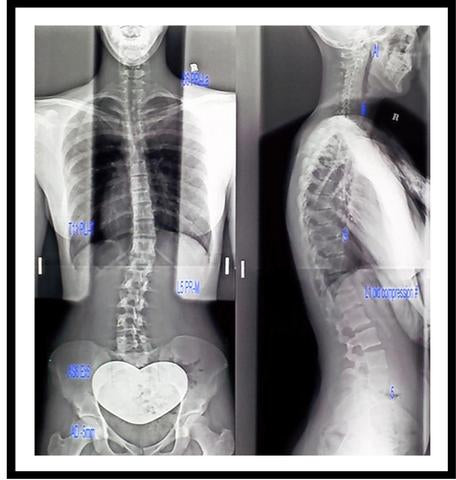

My spinal x-ray

Scoliosis: an abnormal lateral curvature of the spine

When I was 14 years old I had a considerable growth spurt in a short amount of time (11cm in one year). My body had a hard time keeping up with this sudden growth spurt and I was diagnosed with scoliosis.

The abnormal curve and rotation of my spine caused the left side of my back to seize up.